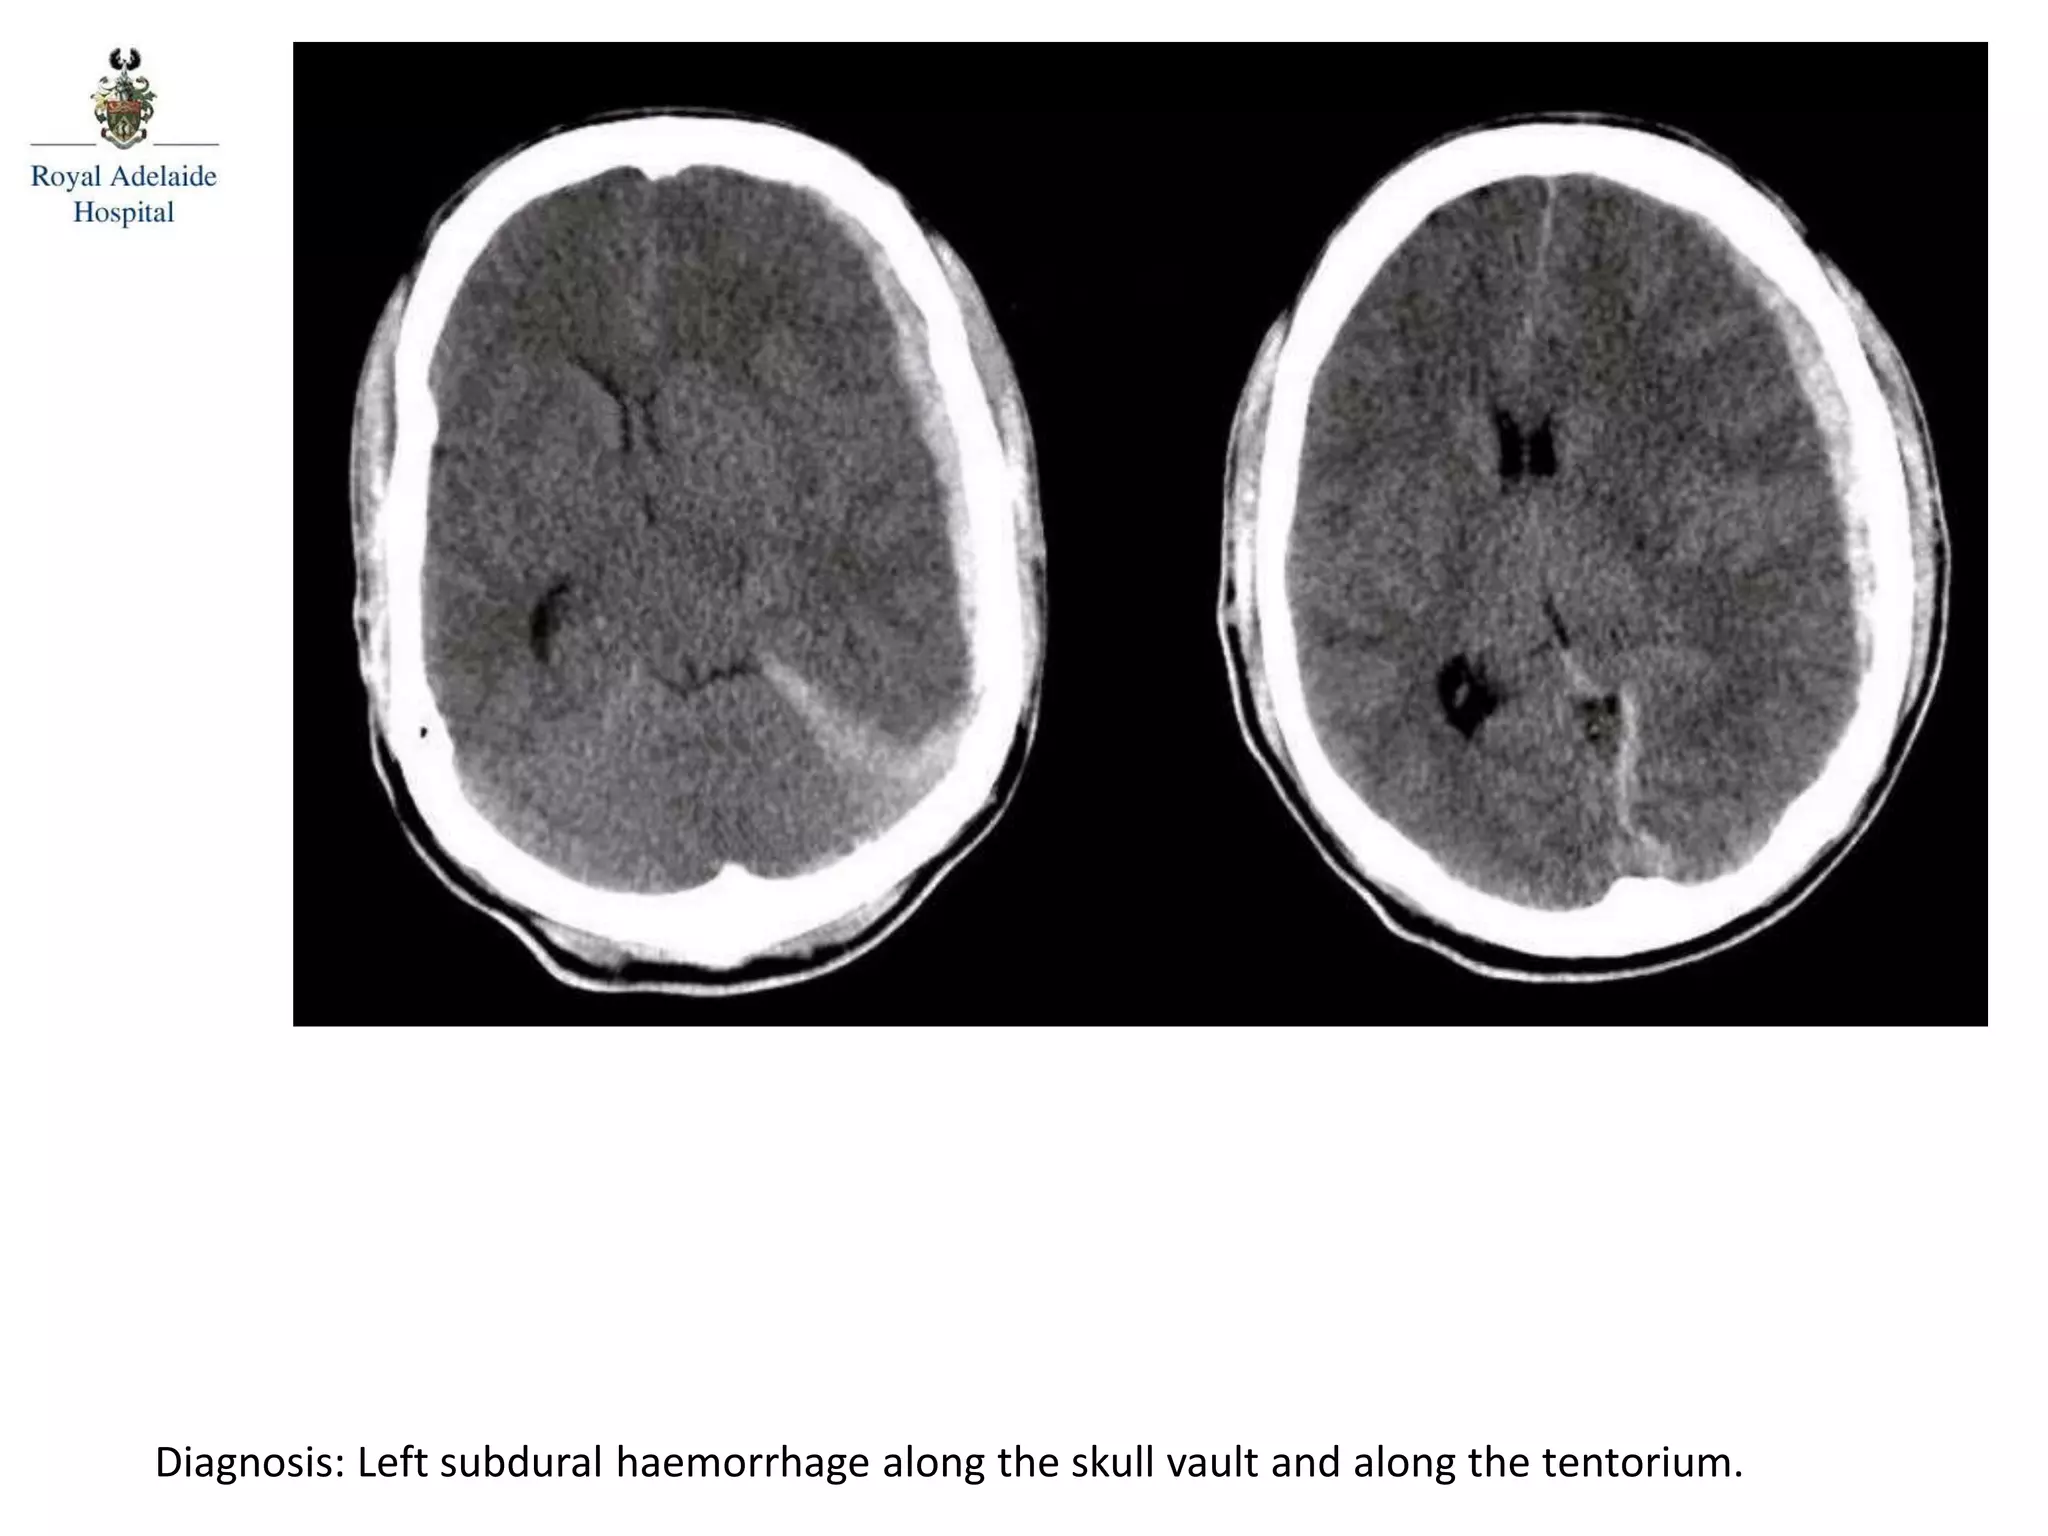

The document outlines multiple diagnoses from head CT cases, including small left basal ganglia bleed likely due to hypertension, various types of subdural and subarachnoid hemorrhages, and evidence of hydrocephalus. It details traumatic origins of some hemorrhages and notes obstructing masses and atrophic changes. Overall, there are significant findings indicating complications related to cerebral hemorrhages and ventricular enlargement.